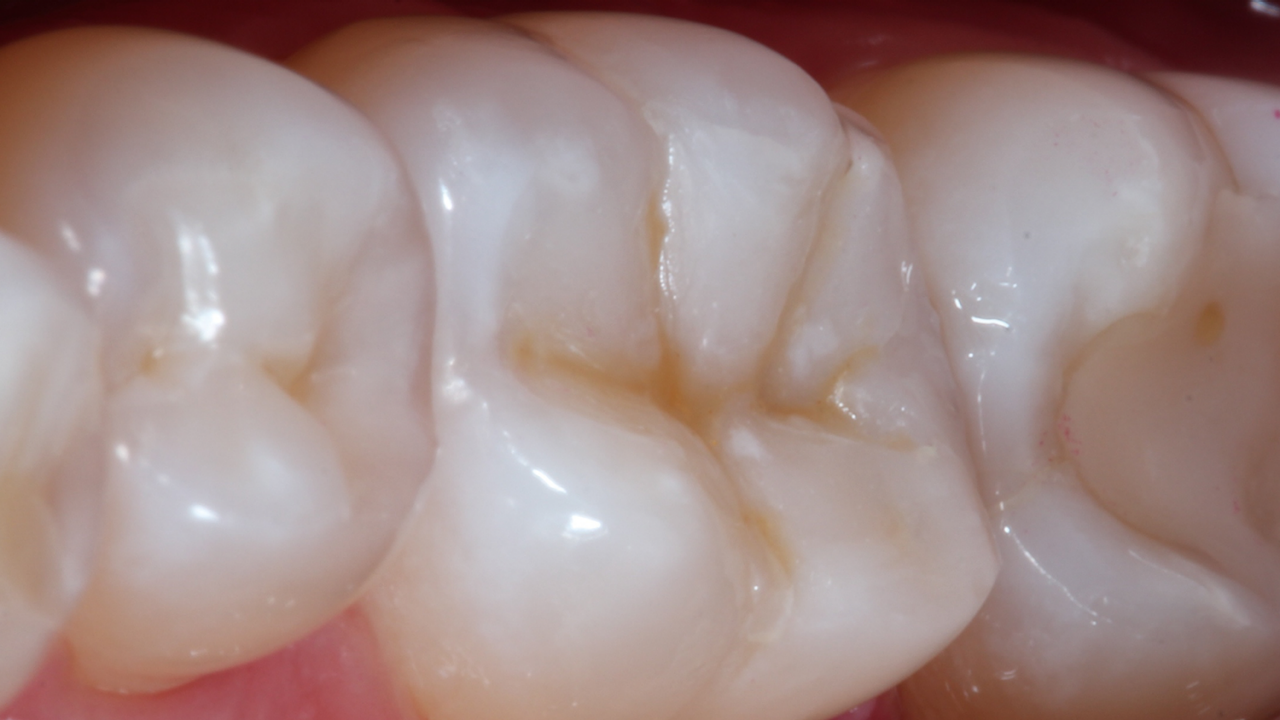

Disto-occlusal Composite Resin Restoration

Case: A 38 year old male patient presented a failed Class II DO composite restoration on a lower molar. After radiographic and clinical examination, the patient was anesthetized, and the old failed restoration, as well as the caries lesion, was removed. The Class II DO cavity restoration was performed using an optimized approach.

Conclusion: In order to reduce the chance of post-operative sensitivity, the selective etching approach was used with a universal adhesive. For perfect to gap free composite adaptation, the low polymerization stress, self leveling, bulk-fill composite SDR flow+ was used. In addition, for accurate proximal contour and optimal creation of a tight contact point, the sectional matrix system Palodent V3 was used.